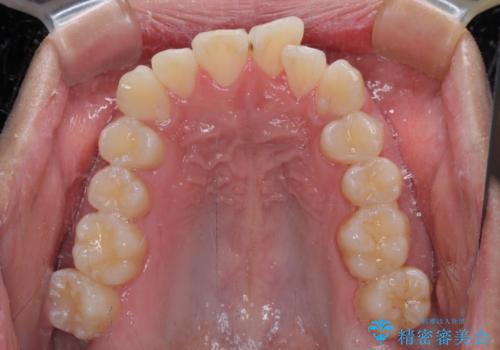

- 前歯のデコボコを治したいとのことで来院された患者様です。

上下顎ともに歯列全体の後方移動とIPR(歯と歯の間を削る)によってデコボコが解消するように設計し、インビザラインにより治療を行うこととしました。